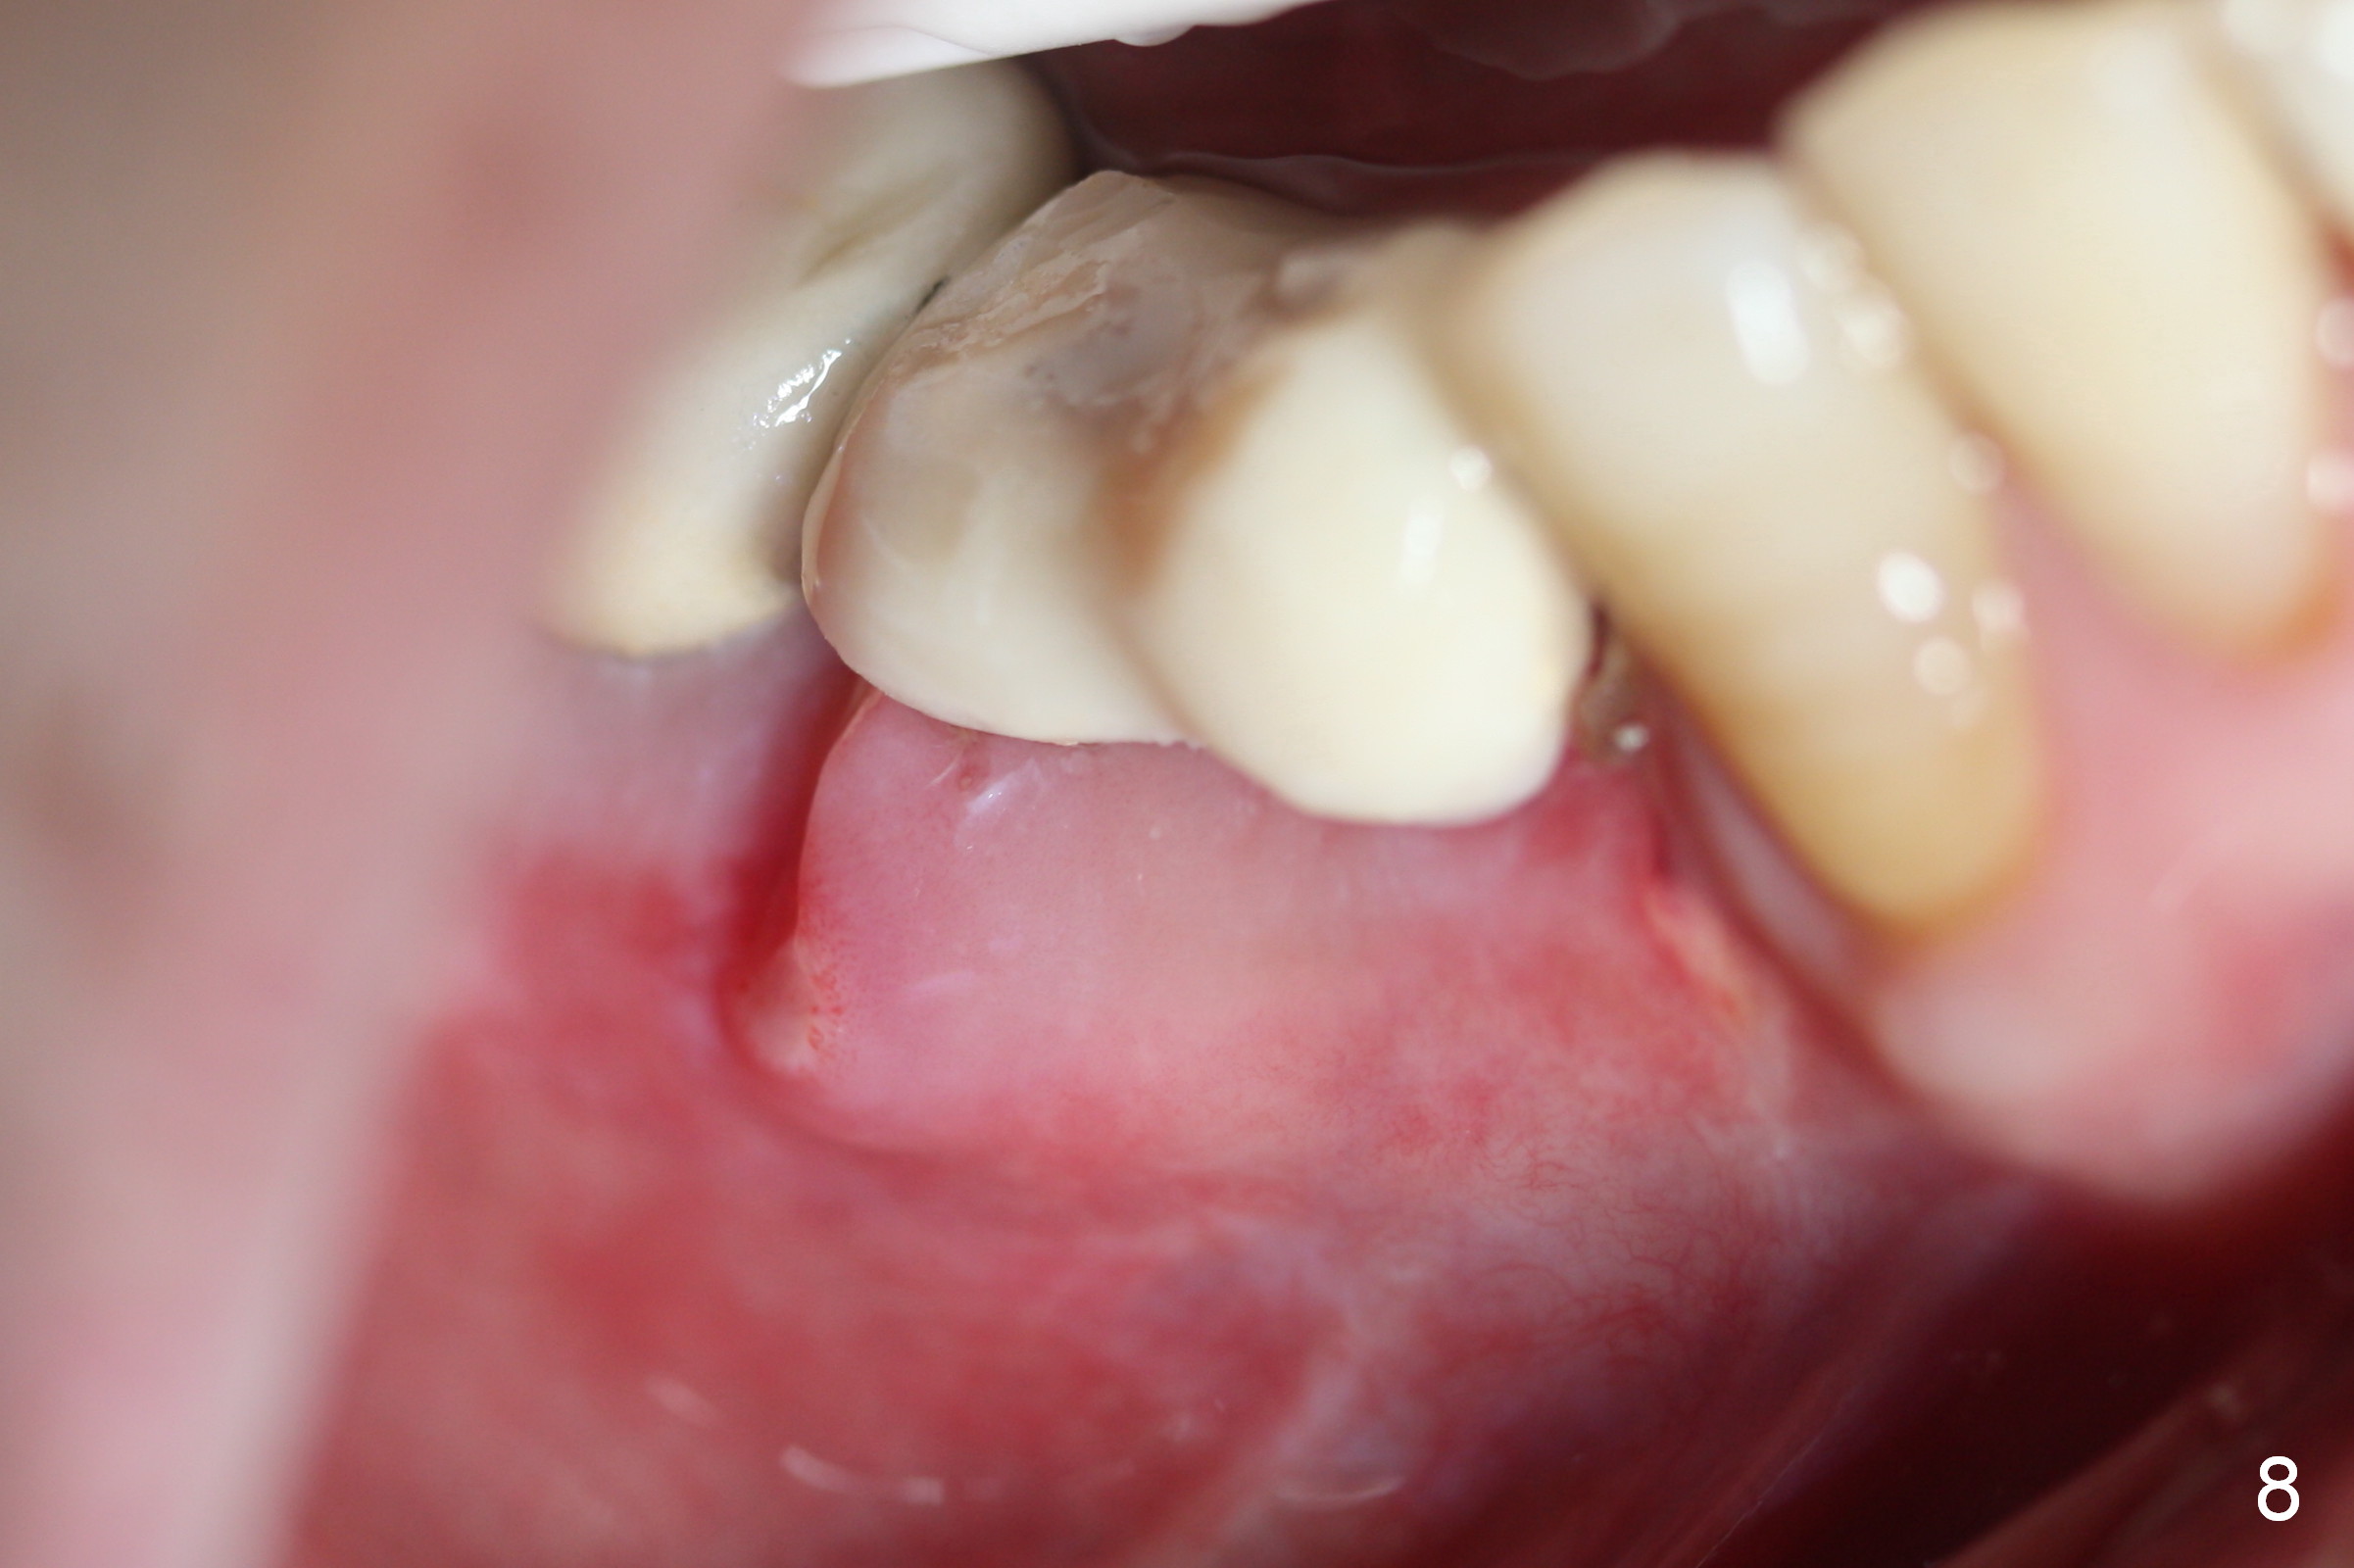

The patient has lost several teeth, which are replaced by removable partial dentures. He wants to have implants in the lower right first because of loss of a buccal clasp over the tooth #30 (Fig.1). When the lower partial is removed, a narrow soft tissue band is visible in the edentulous area. The hard tissue ridge is approximately 3 and 5 mm buccolingually at the sites of #28 and 29, respectively (Fig.3 after initial osteotomy). To place 2 adjoining implants at the same level, the treatment plan is modified: a 3 mm 1-piece implant will be placed at #28, while the plan at #29 remains the same: a 4.5 mm 2-piece implant.